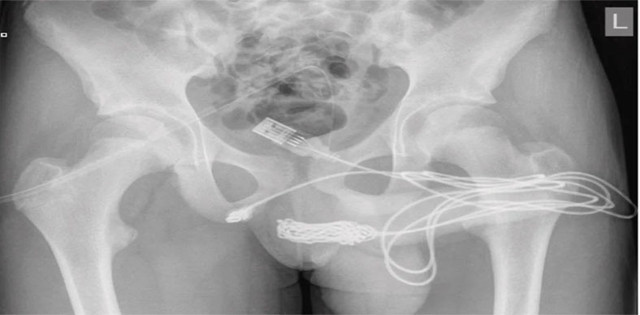

USB kablosu şikayeti ile hastaneye başvuran 15 yaşındaki çocuk Londra Üniversitesi hastanesine kaldırıldı. İsmi açıklanmayan gencin durumu doktor raporların göre "USB kablosunun iki distal portunun dış üretral kanaldan dışarı çıktığı ve düğümlü telin orta kısmının üretra içinde kaldığı tespit edildi. Hasta, ruh sağlığı bozukluğu öyküsü olmayan, aksi halde zinde ve sağlıklı bir ergendi." denilerek açıklandı.

İlk önce metal bir çubukla çıkartılmaya çalışılan kablo daha sonra düğümlendiği için çocuk acil olarak ameliyata alındı. 15 yaşındaki çocuğun Ultrason rehberliğinde suprapubik bir kateter yerleştirildi ve yaklaşık 700 ml hematürik idrarı boşaltıldı. Rapora göre, cerrahlar kablonun bir ucunu anüsüne yakın bir kesiden ve geri kalanını penisinden çıkardı.